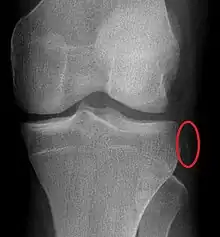

A Segond fracture seen on X-ray

As the injury may have self-reduced before arrival at hospital, the diagnosis may not be readily apparent.[2] Diagnosis may be suspected based on the history of the injury and physical examination[5] which may include anterior drawer test, valgus stress test, varus stress test, and posterior sag test.[5] An accurate physical exam can be difficult due to pain.[5]

Plain X-rays, CT scan, ultrasonography, or MRI may help with the diagnosis.[2][11] Findings on X-ray that may be useful among those who have already reduced include a variable joint space, subluxation of the joint, or a Segond fracture.[5]